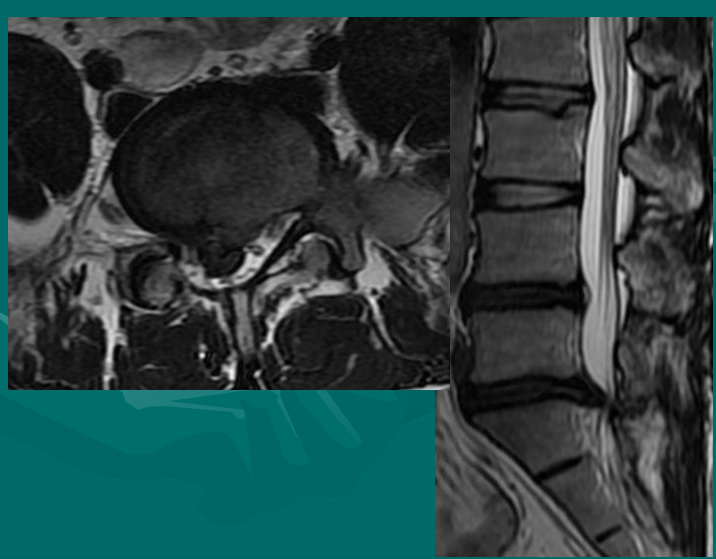

位于椎体之间的椎间盘应是白色的(含水多)。注意黑颜色(脱水的)的L5椎间盘(L5与骶骨之间的椎间盘),这代表了中度到重度的退化性椎间盘病。

后纵韧带(PLL小蓝箭头)在图像中表现为沿着每个椎体及椎间盘后缘垂直向下的黑线。有意思的是,尽管此病人有一个9mm的椎间盘突出(HNP),骨质有一定的翘起,在椎间盘平面以上可见髓核物,但后纵韧带仍然包容着突出的髓核物而没有游离出。这种情况在学术上被称作一个大的包容性椎间盘突出。

硬膜囊(红星)表现为“超白色”结构,填充在椎体后方的中央椎管内。此囊袋内有可自由浮动的由运动神经纤椎及感觉神经纤维共同组成的脊神经根(马尾)。

黄韧带(绿星)位于每个椎骨之间,增强脊柱的稳定性。此结构可变大或增厚,助长年长者易患的中央型椎管狭窄的形成。